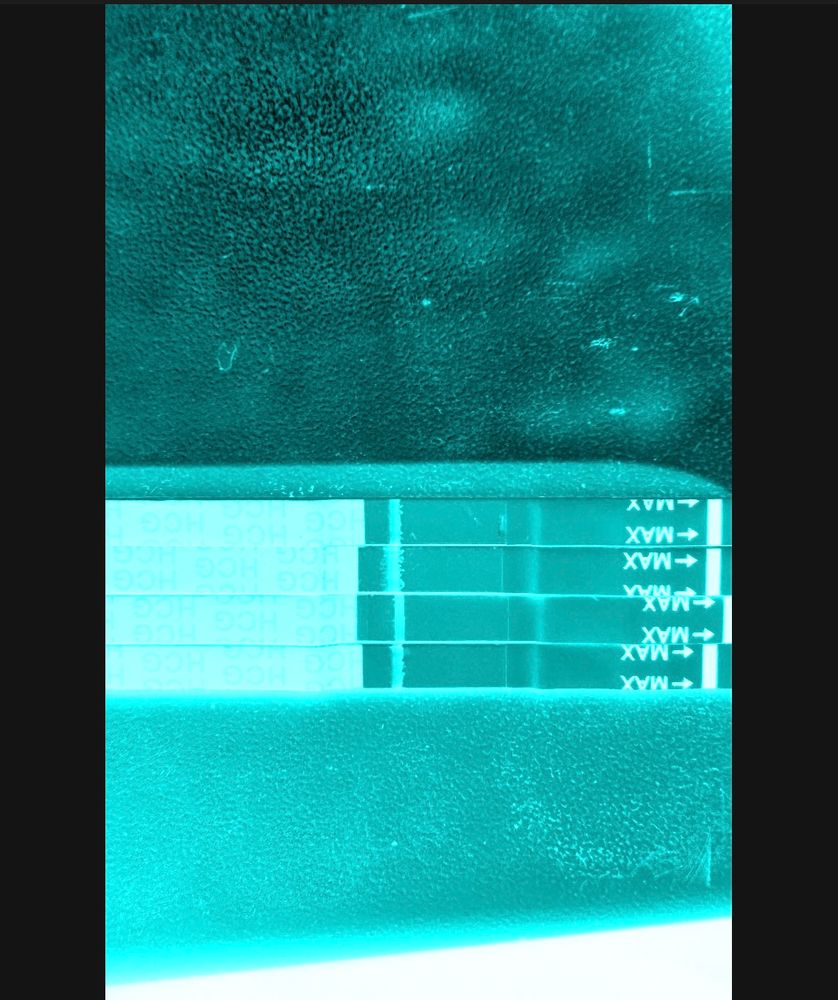

Девочки делала тесты начиная с 8 пдо , не знаю зачем 😂тапки не кидать ) последний тест 11пдо , я вижу тень , все тесты с одной пачки мама чек. Что думаете ?

Девочки делала тесты начиная с 8 пдо , не знаю зачем 😂тапки не кидать ) последний тест 11пдо , я вижу тень , все тесты с одной пачки мама чек. Что думаете ?

Тут явно место под полоску на всех. Для 10-11 ну это совсем слабо. Вечером повторите. Мои всегда вечером ярче. Мало ли, может и у вас так